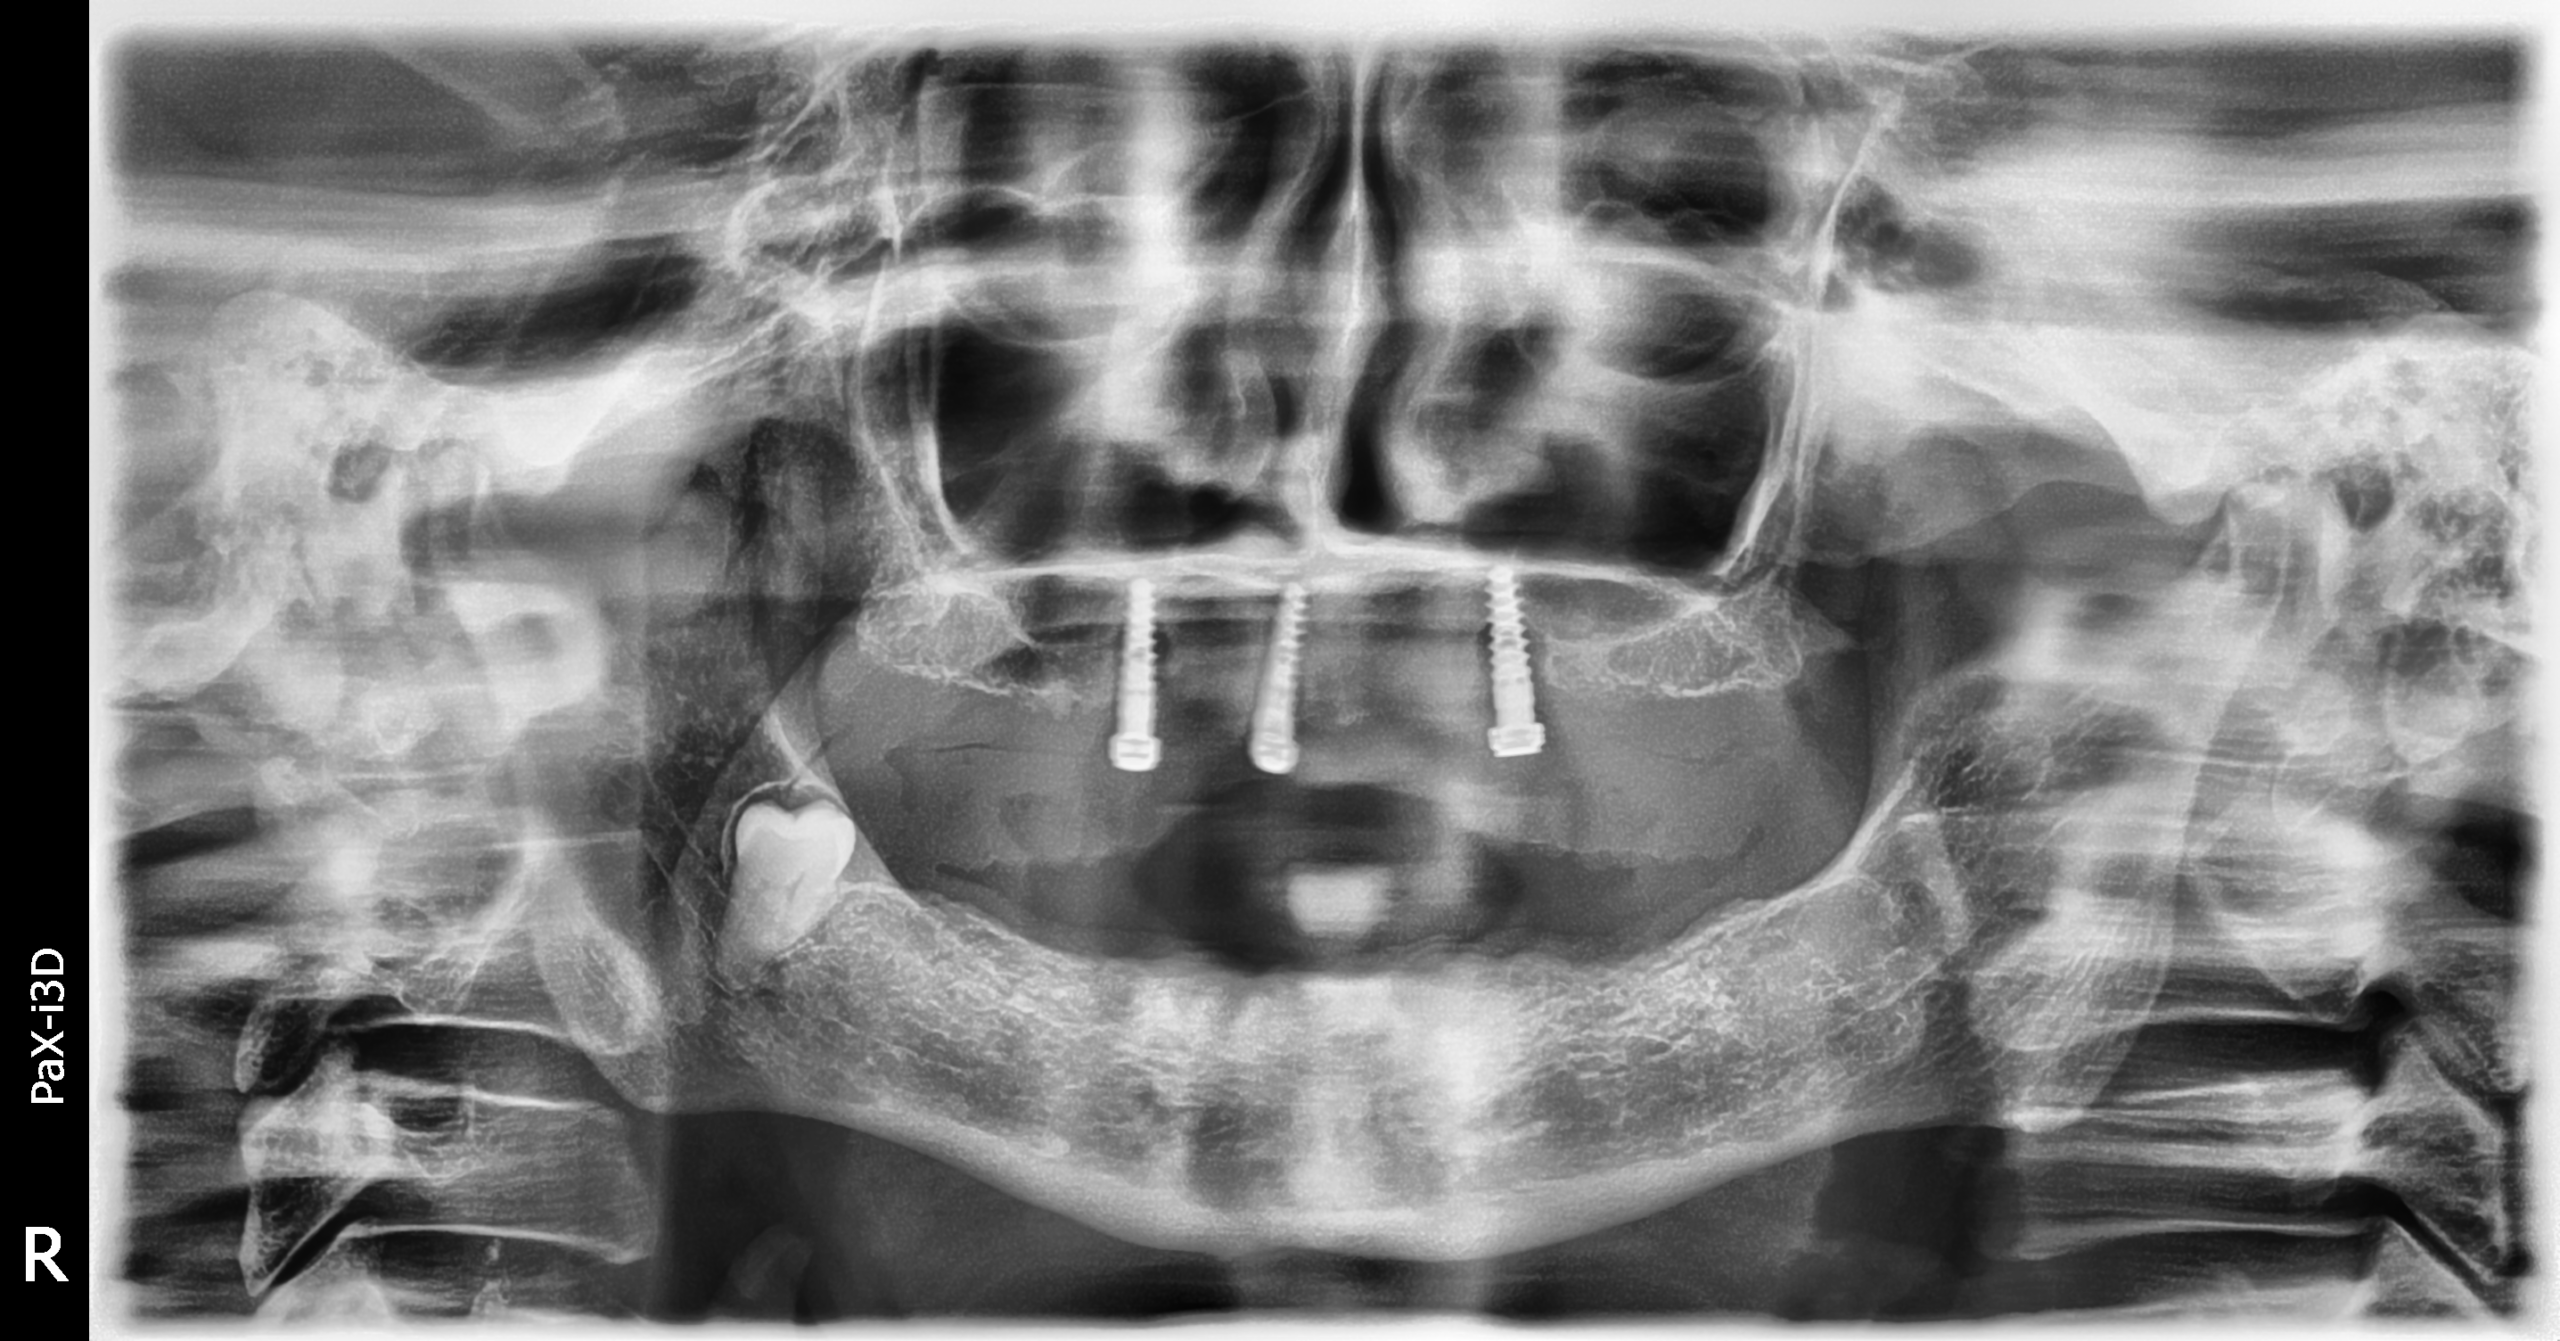

Implantes PHIA

Secuencia de imágenes RX, antes y después de la inserción de implantes PHIA en la parte superior de la boca.

Paciente varón de 82 años.

- Radiografía previa a la operación.

- Extracción implantes parte superior.

- Colocación implantes Radhex PHIA parte superior.